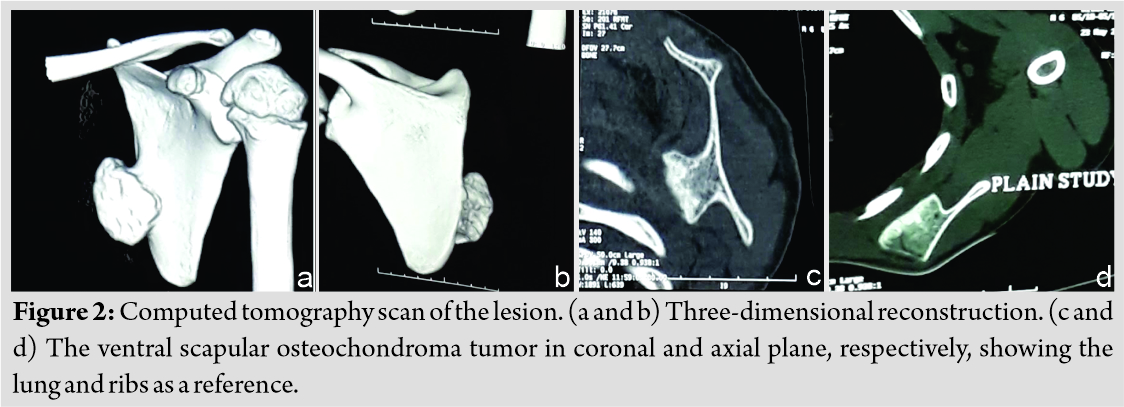

On examination, there was a single swelling of approximately 3 × 3 × 2 cm3 over medial border of the left scapula. Overlying skin was normal. It was hard in consistency with well-defined margin and irregular surface. It was non-tender, immobile, arising from underlying bone, and non-adherent to skin. It was non-fluctuant and non-compressible. Pseudo-winging of scapula was present as shown in (Fig. 1) with wall test because there was no tenderness, neurological examination was within normal limit, and range of movement in cervical spine along with extremity was normal. His activity of daily living was not affected. There were no signs of compression of nerves, vessels, or lymphatic system. No lymph nodes were palpable. Distal neurovascular status was within normal limit. There was no audible or palpable crepitus. Range of movement of the shoulder and cervical spine was normal. The patient was referred with an anteroposterior view radiograph and a computed tomography (CT) scan. No further radiological workup was attempted in view of radiation exposure. The CT scan demonstrated a well-corticated bony excrescence arising from ventral surface of the left lower part of body of scapula near inferior angle suggestive of exostosis (Fig. 2). A working diagnosis of VSO was made. Excision of lesion was principally done for mechanical reasons and secondarily for pathologic assessment. It was done under general anesthesia with patient in prone position. Shoulder was rotated internally, which helped lift medial border of scapula. A 5 cm incision was given along inferomedial border. A muscle splitting approach of trapezius and rhomboid was used. En bloc excision of VSO was done. To prevent complications, meticulous dissection was done and hemostasis was obtained. It was removed as a single block to prevent seeding. No remnants were left. Sessile VSO of 3 × 3 × 1 cm3 was sent for histopathological assessment. The tumor was hard. It was composed of bone covered by a thick cartilage cap, as shown in (Fig. 3, 4). Thorough irrigation was done and the wound was closed in standard fashion. The surgery was over in 45 min.

VSO is diagnosed frequently by clinical assessment and imaging, whereas confirmation is done by histopathologic evaluation [17]. VSO may be difficult to identify clinically pertaining to its location. One may miss it on plain radiographs [9]. CT or magnetic resonance imaging (MRI) helps establish a diagnosis [16]. CT scan helps in characterizing lesion and planning treatment. MRI is usually reserved for malignant transformation suspicion [14]. MRI aids in measurement cartilaginous cap thickness. A cap thinner than 1 cm usually indicates a benign lesion. Thickness of more than 2 cm generally relates to malignant change [2]. A cartilaginous cap with thickness <1 cm in biopsy indicates a benign condition, whereas a cap thicker than 2 cm should raise concern for malignant transformation [5]. In our case, the cartilaginous cap thickness was 0.3 cm.